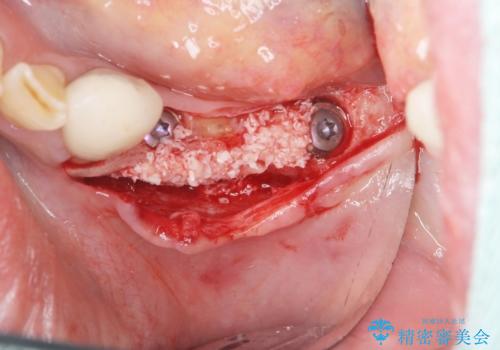

入れ歯を外し、またしっかりと噛んで食事を楽しめるようになるためにインプラントによる治療を計画します。

- 91万円(ストローマンインプラント×2・骨造成・チタンカスタムアバットメント×2・フルジルコニアクラウン×3)費用は治療当時の料金となります

- 外科手術のため、術後に痛みや腫れ、違和感を伴います